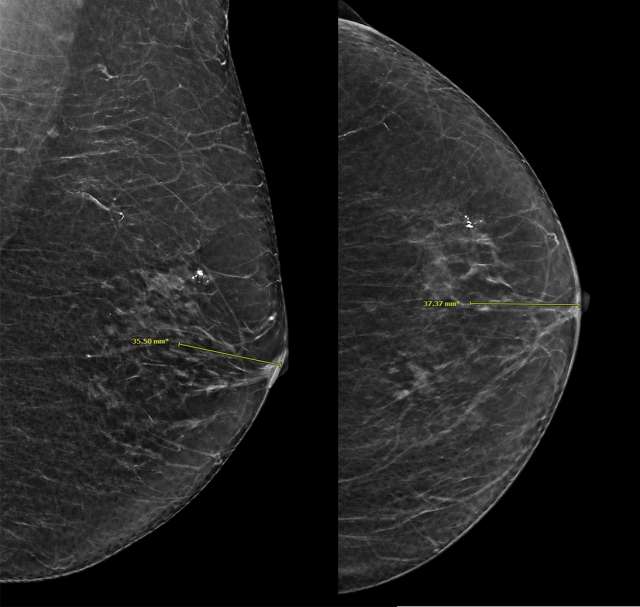

Distance from the nipple measures the distance from the lesion to the nipple to further localize the lesion on different mammographic views (Figure 8).

Screening Mammogram: Breast Lesion Localization Figure 8

Figure 8. Measuring the distance of suspicious breast calcifications from the nipple.